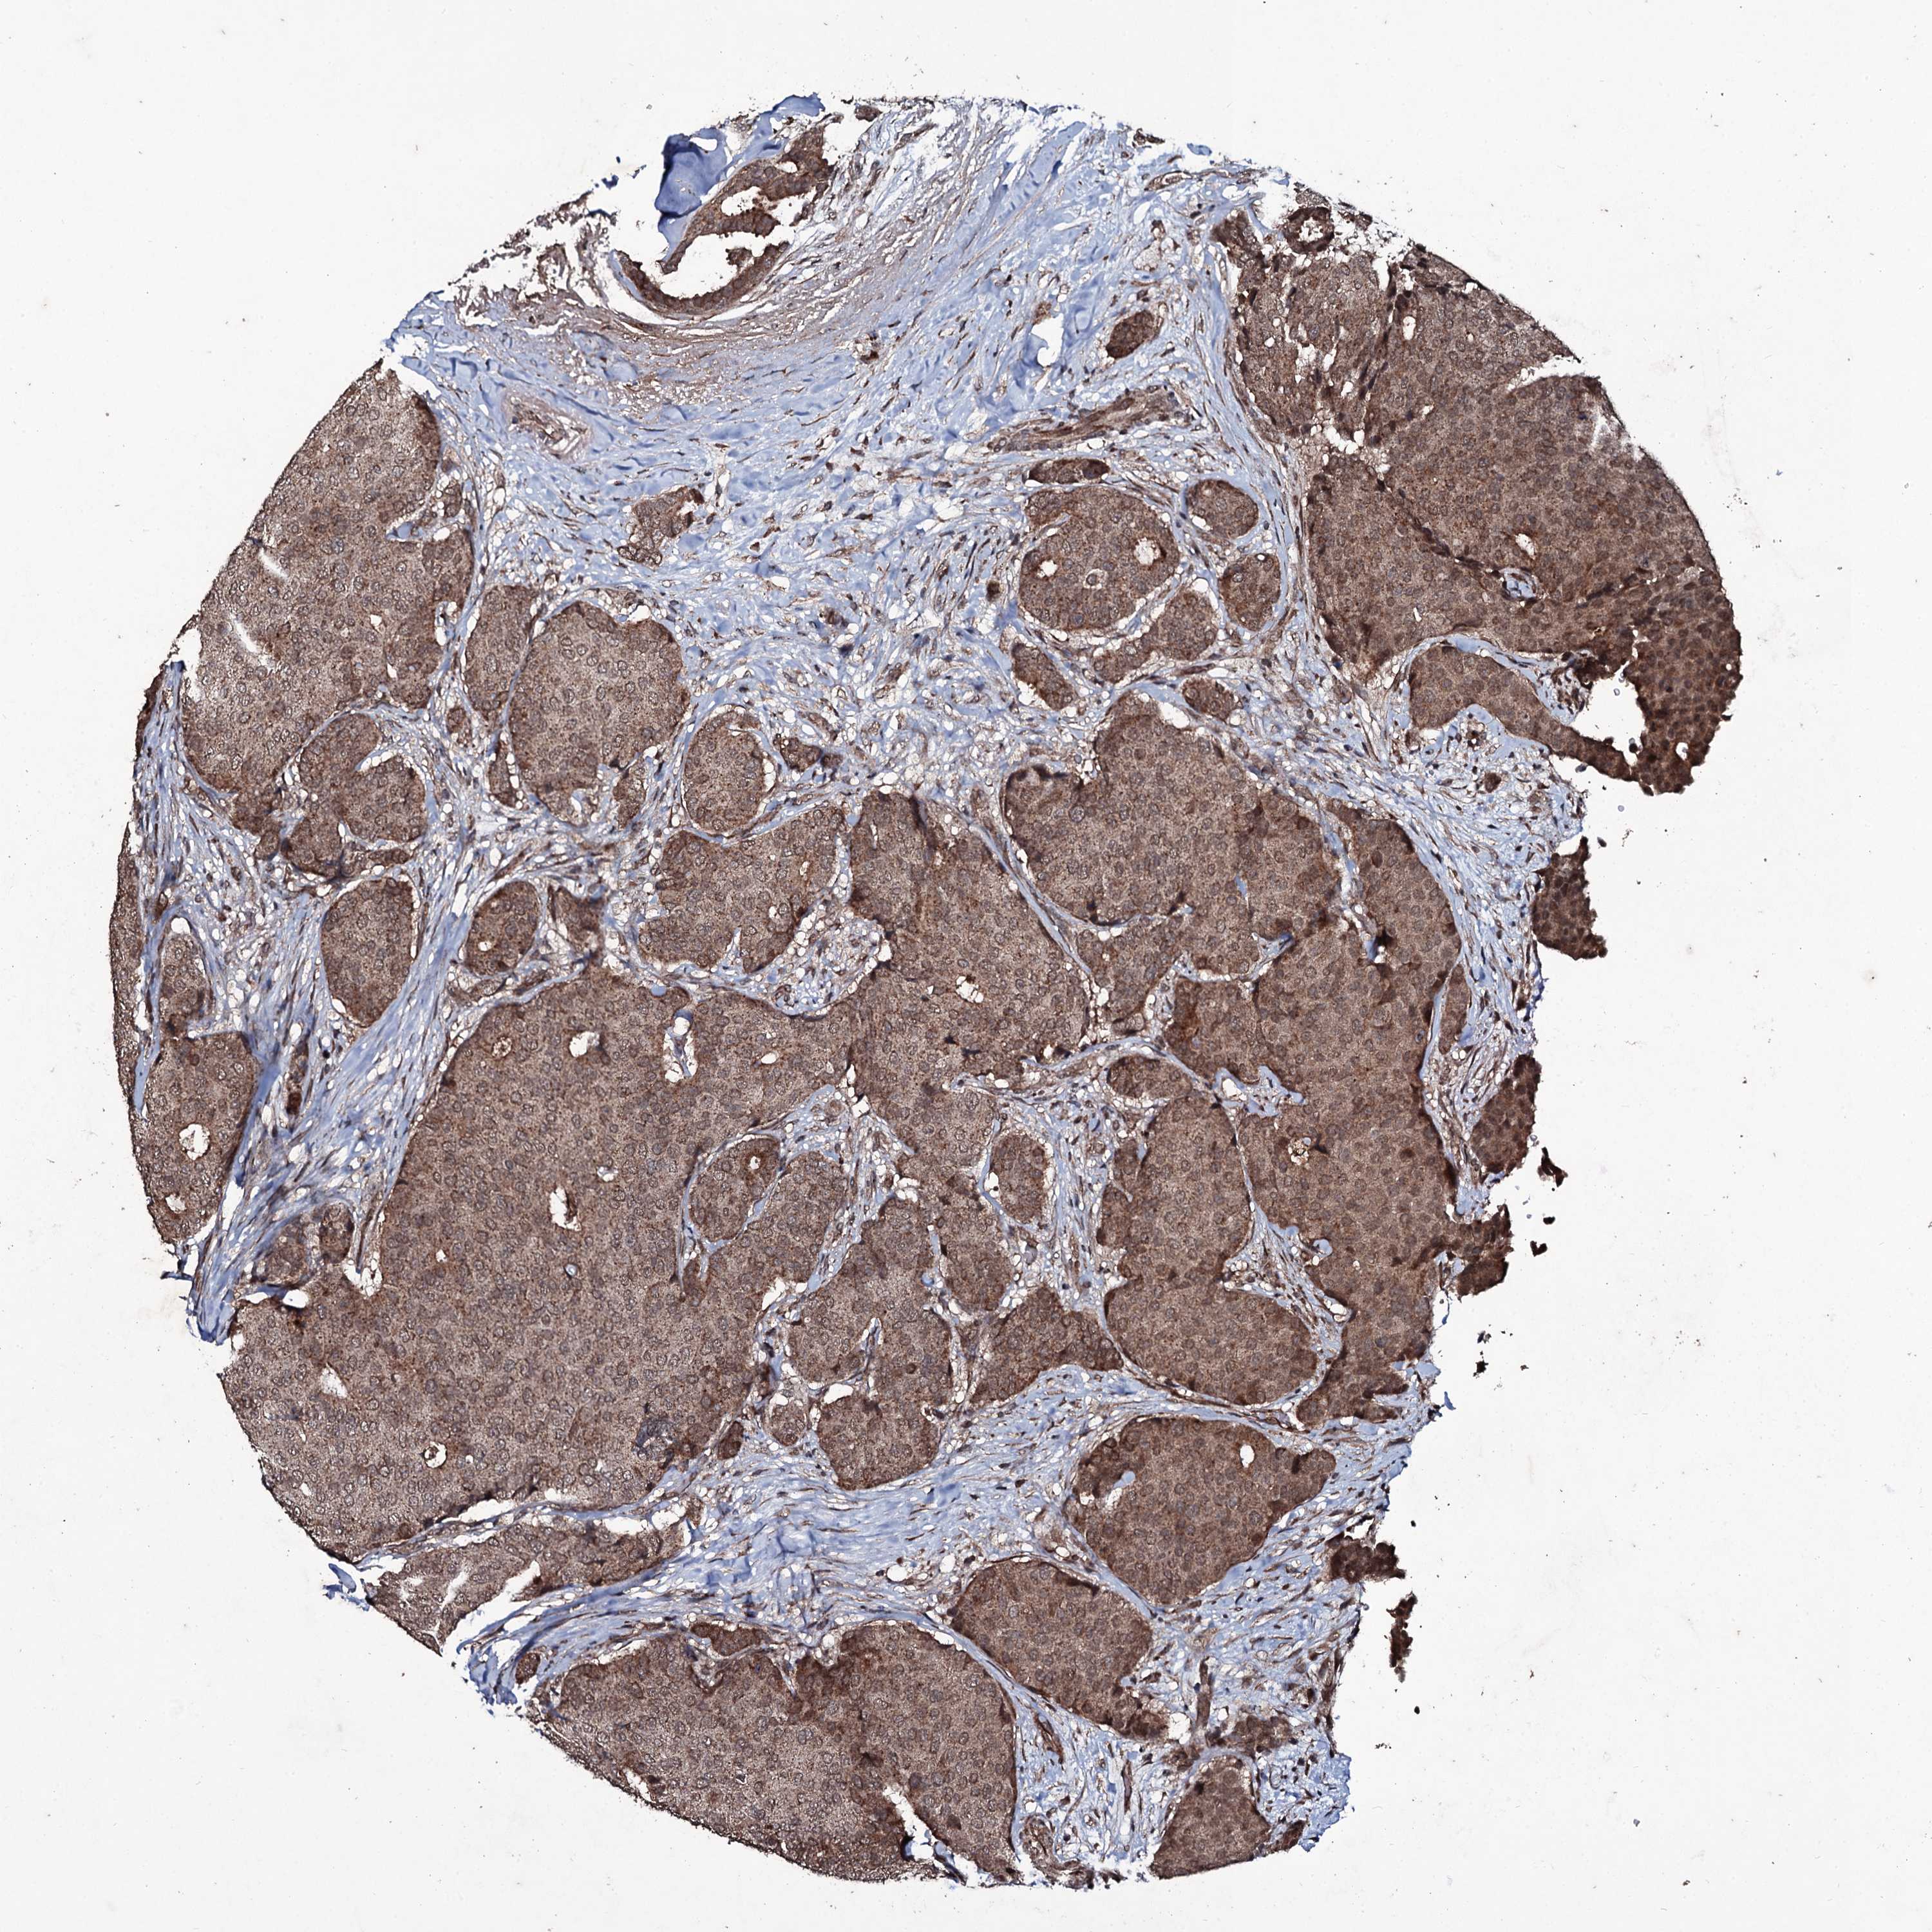

CANCER BREAST CANCER Show tissue menu

BRCA TCGA BRCA VALIDATION PROTEIN EXPRESSION